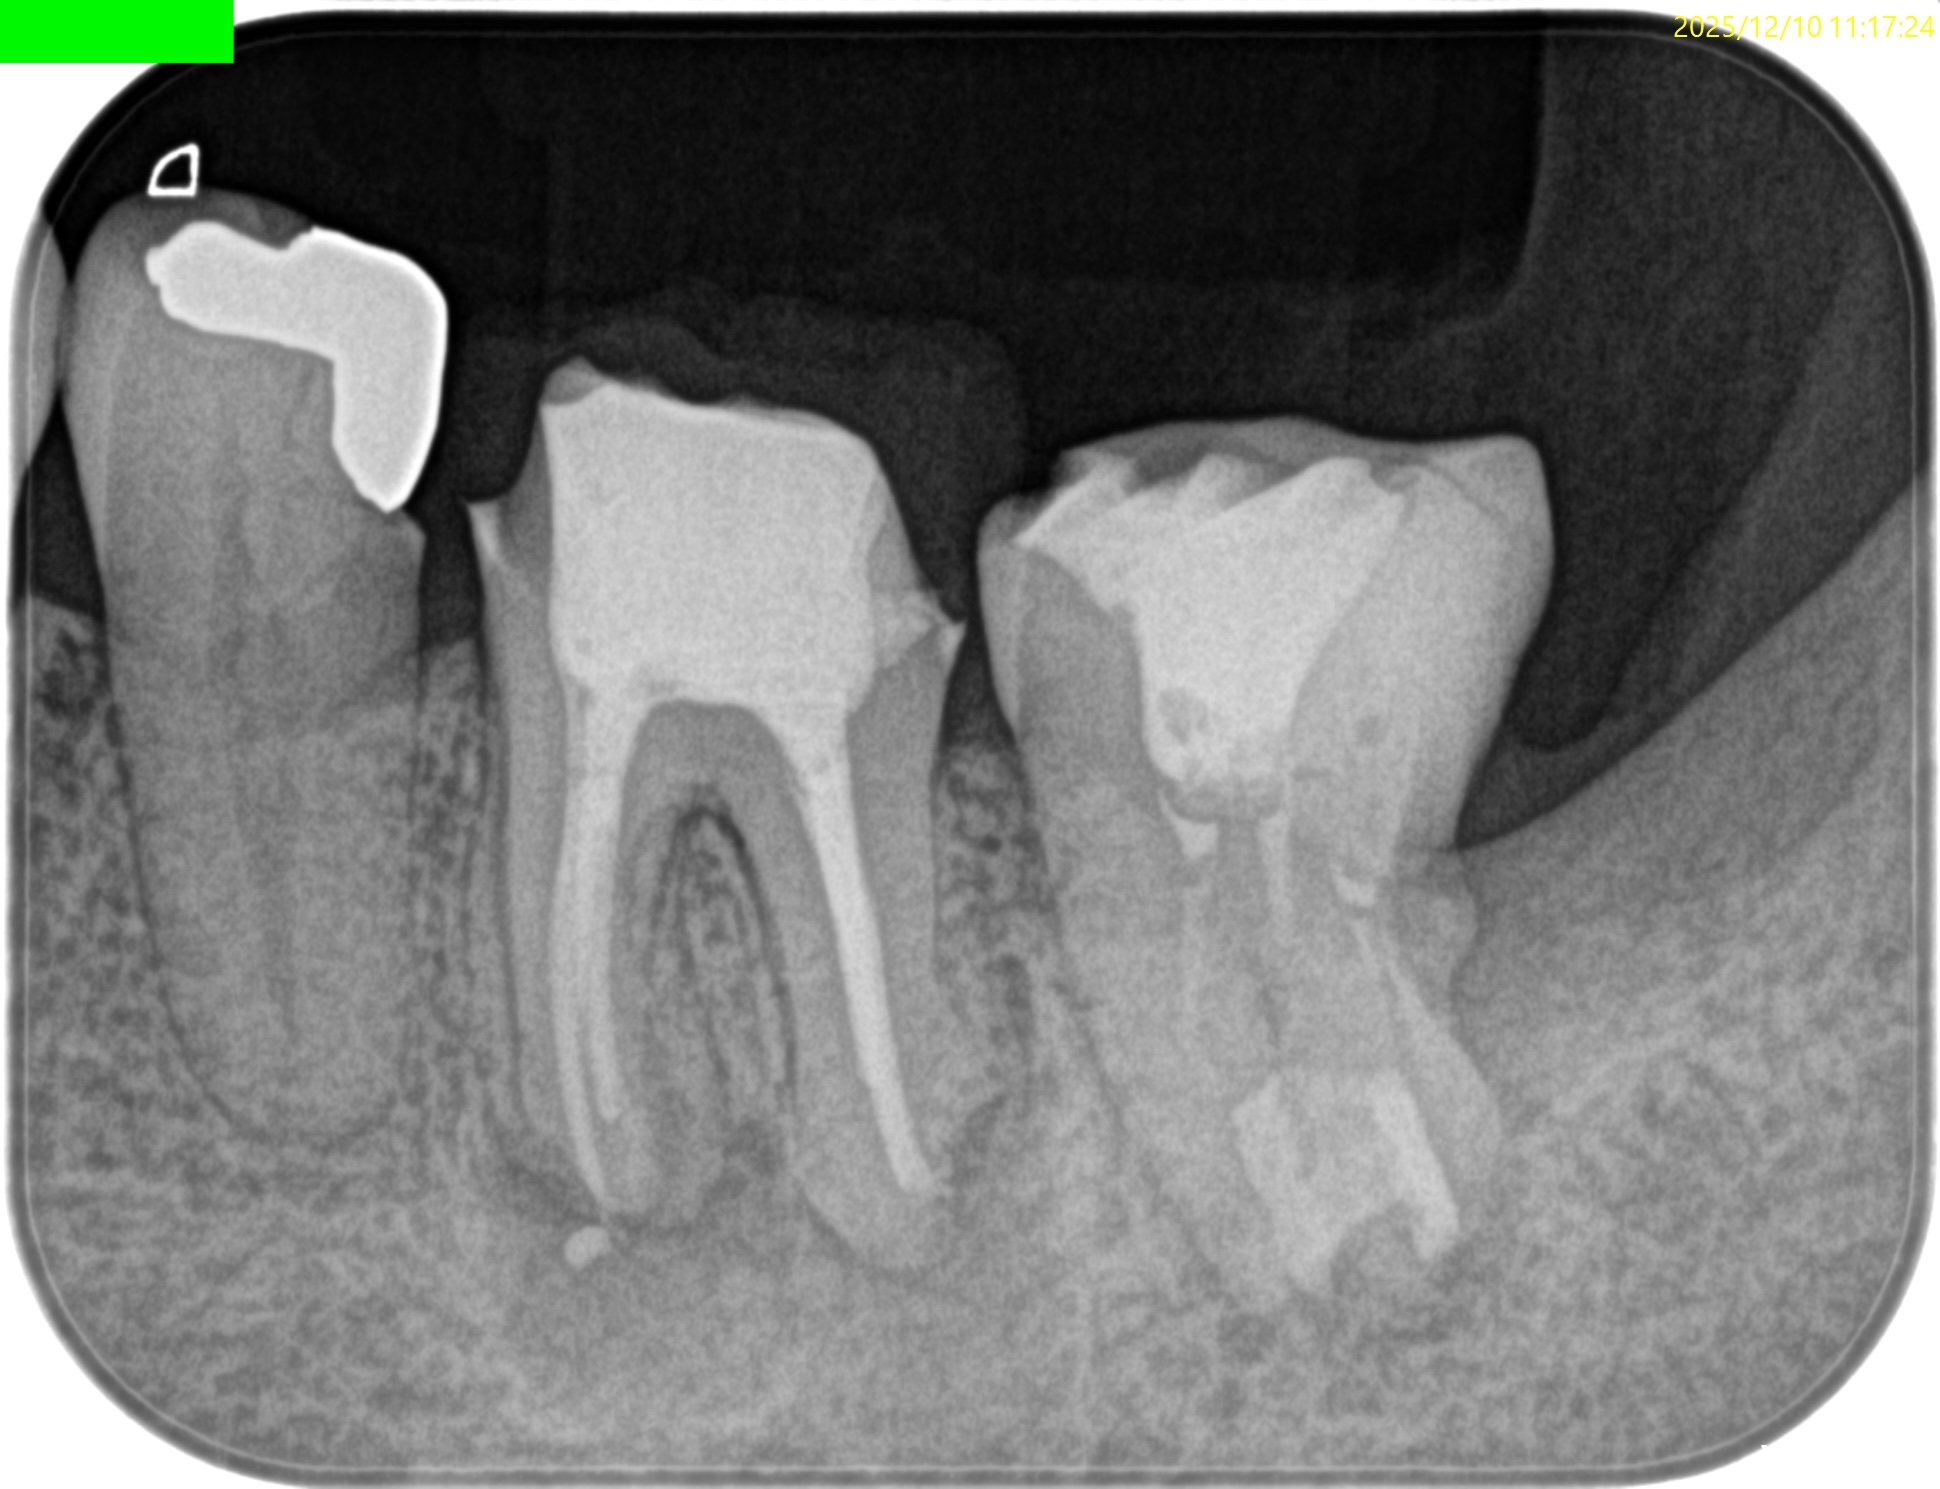

PA(2025.12.10)

CBCT(2025.12.10)

ML

MB

D

遠心方向から見ると、

絶望的な状態であることがわかる。